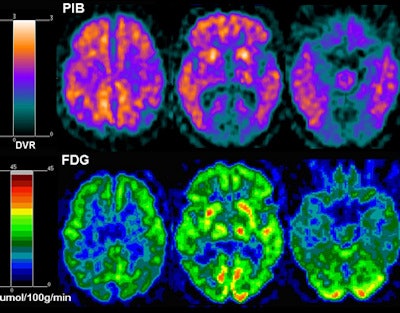

FDG-PET was used to detect glucose metabolism in the brain, while PiB-PET was used to detect amyloid deposition. Both tracers are commonly used in normal elderly people to assess the risk of developing Alzheimer's; however, they had not been used to determine a relationship between Alzheimer's and sleep-disordered breathing in this population.

To determine a correlation between sleep apnea and Alzheimer's, the researchers measured standardized uptake value ratios (SUVRs) in different regions of the brain using the FDG-PET and PiB-PET images. The brain areas included the middle temporal lobe, inferior parietal lobule, lateral temporal lobe, posterior cingulate cortex/precuneus, prefrontal cortex, occipital cortex, and thalamus.

The resulting SUVRs (see chart) suggest an association between sleep-disordered breathing and glucose hypometabolism in regions of the brain vulnerable to Alzheimer's disease, "which may indicate increased risk for Alzheimer's in cognitively normal elderly," according to the authors. Also, while the whole brain was hypometabolic, the effect was stronger in Alzheimer's-vulnerable regions.

"What you see are the areas that are usually vulnerable for Alzheimer's, such as the middle temporal lobe or the prefrontal cortex," Osorio said. "If the person is going to develop Alzheimer's, those areas start to show hypometabolism years before disease onset."